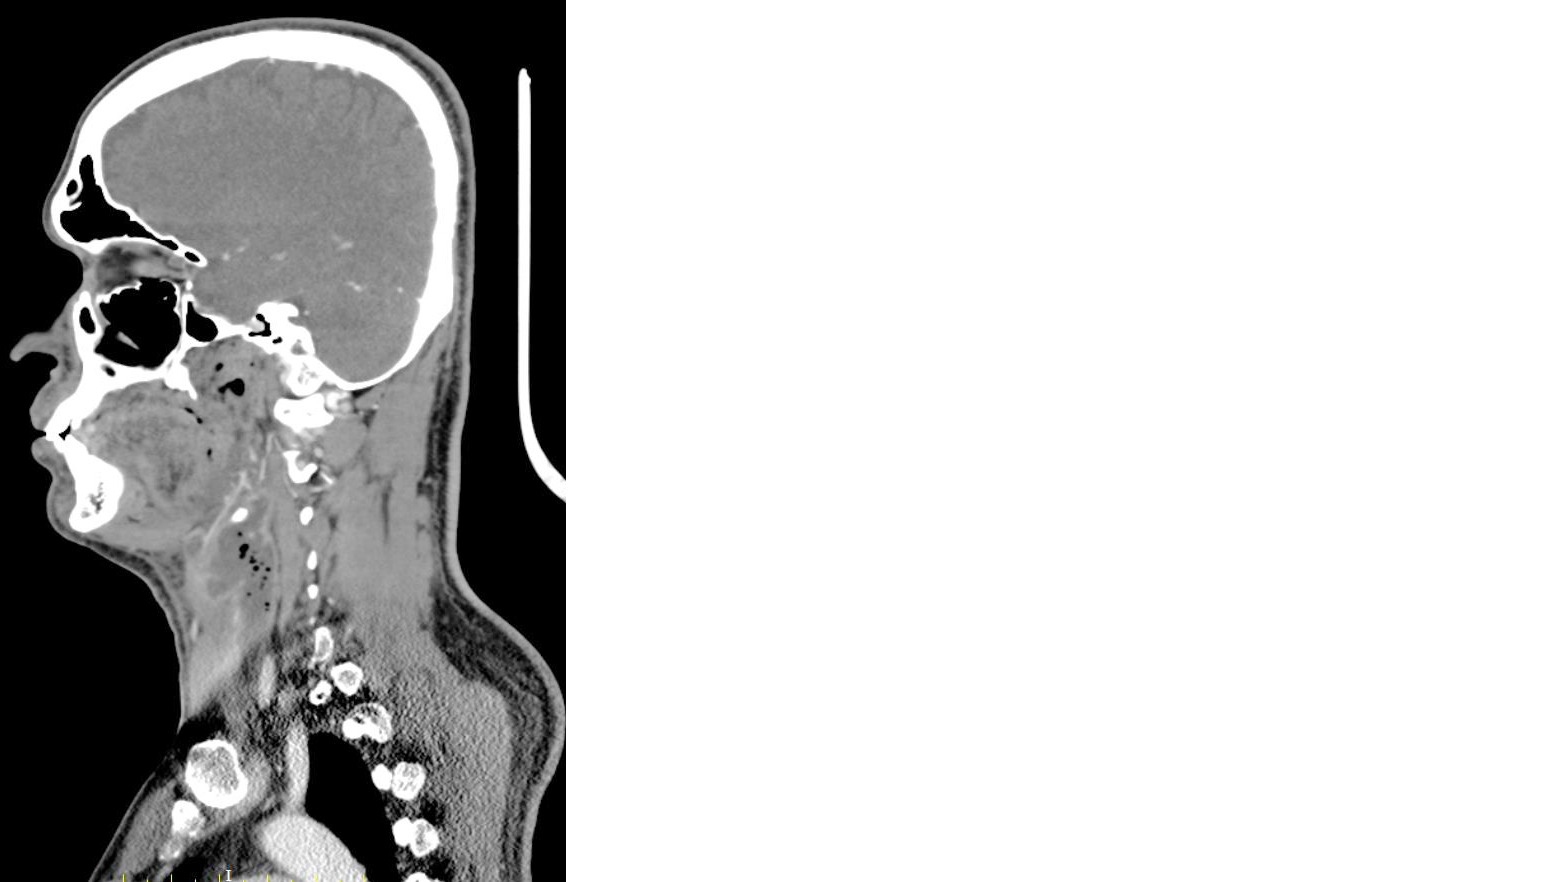

A follow-up contrast-enhanced CT scan of the neck and chest revealed persistent collections within the deep neck spaces, including the retropharyngeal and danger spaces, with extension into the mediastinum and partial reduction of the masticator space component (Figure 3). Narrowing of the left internal jugular vein was also noted.

Figure 3: CT neck (sagittal view) showing neck abscess extending into retropharyngeal, danger space and mediastinal space with reduction in masticator space component.